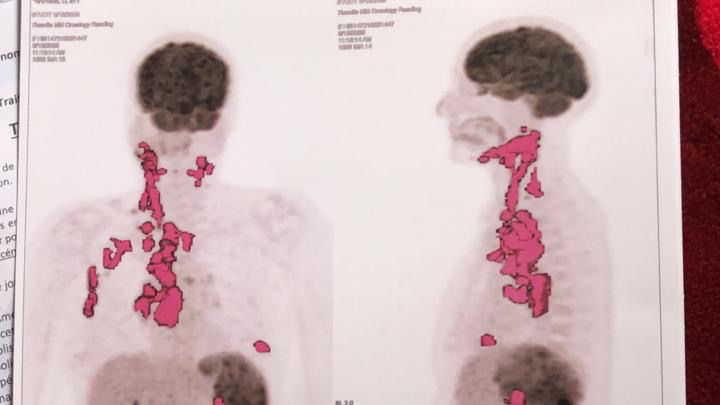

Je m’appelle Hajar, je vis et travaille à Montréal, mais ma maman, qui ne vit pas avec moi, traverse une période très difficile. Elle a été diagnostiquée avec un lymphome de Hodgkin de stade 3, une maladie grave qui nécessite un traitement coûteux : médicaments, examens et séances de thérapie. Malheureusement, ces frais sont un fardeau trop lourd pour notre famille.

My name is Hajar. I live and work in Montreal, but my mother, who doesn’t live with me, is going through a very difficult time. She has been diagnosed with stage 3 Hodgkin’s lymphoma, a serious illness that requires expensive treatment, including medication, tests, and therapy sessions. Unfortunately, these costs are an overwhelming burden for our family.